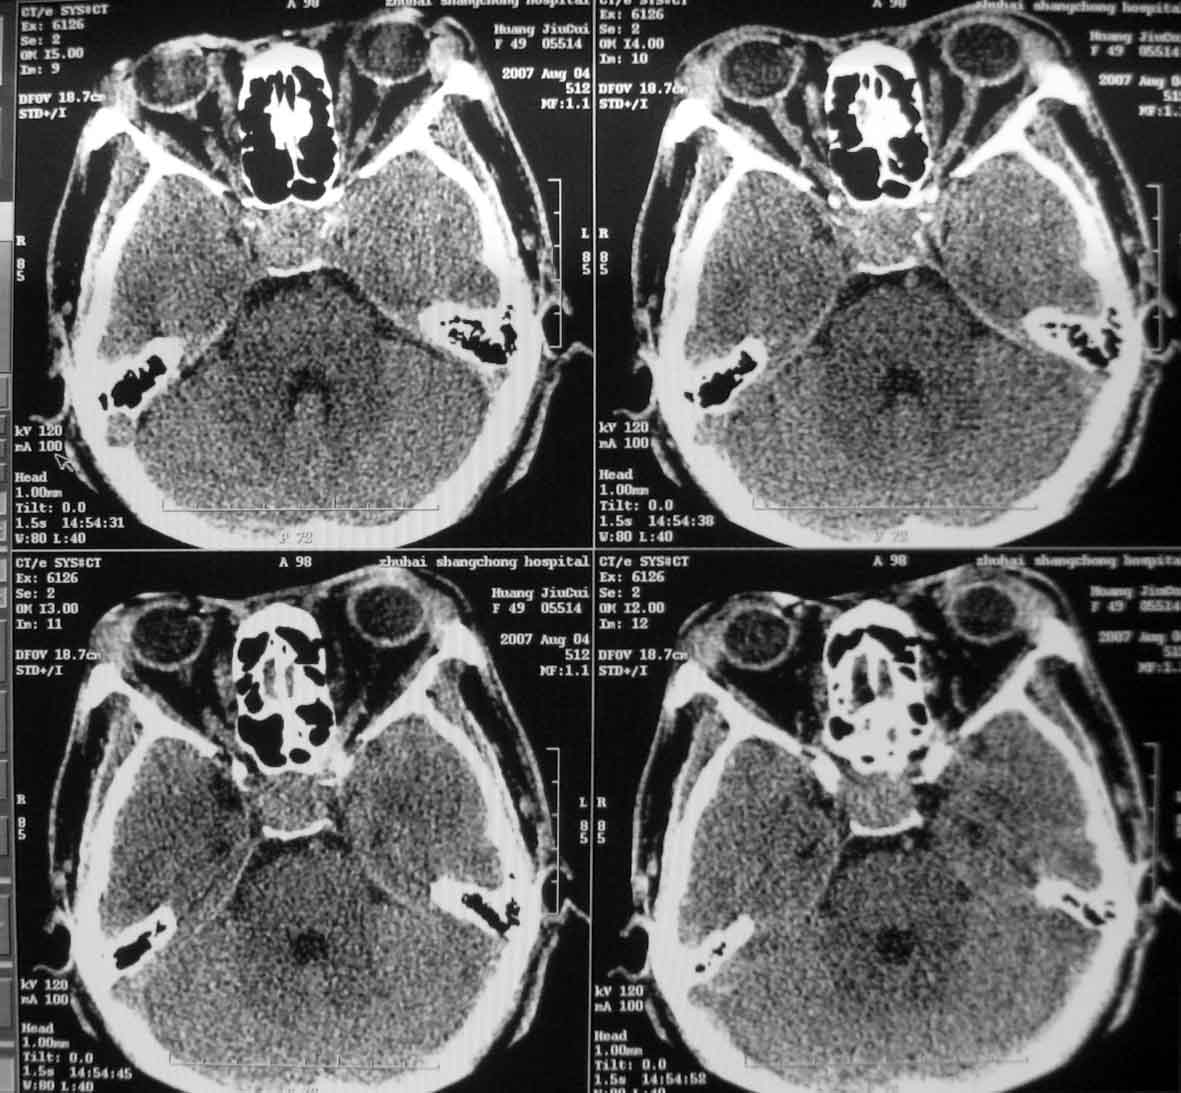

标题: CT9522:F49Y,脑垂体肿瘤 [打印本页]

垂体窝内均匀软组织密度肿块,前后床突及左侧鞍底受压,无明显骨质破坏,结合临床有指端肥大病史,支持考虑垂体腺瘤。

结合病史,典型的垂体大腺瘤------垂体增大,蝶鞍扩大,鞍底下陷,鞍背变薄,前床突骨质又吸收

结合病史,典型的垂体大腺瘤,建议做个磁共振,可能有海绵窦受侵,尤其是右侧

垂体腺瘤建议mri检查,海绵窦受侵犯.